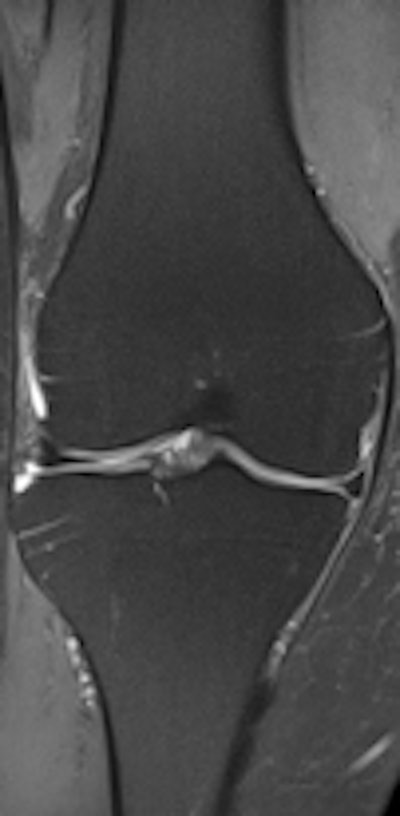

Expanding on its global R&D footprint that includes a new high-tech facility in Suzhou, China, Philips has developed a reliable and simple to use machine for developing markets. The Multiva 1.5-tesla unit is designed to ease patient discomfort and increase productivity by reducing the time spent setting up an examination. It features the FlexStream workflow system, which enables efficient handling of coils for head, spine, musculoskeletal, and neurovascular examinations, allowing a reduction of up to 40% in the time it takes to position the patient and coils before securing an image, according to the manufacturer.

Another feature of the Multiva system is SmartSelect software, which automatically determines which coils and elements should be activated to yield the maximum SNR in the region of interest for greater efficiency and higher image resolution. Additionally, a large neurovascular coil design allows patients to use headphones during their examination, which can help improve patient comfort. These improvements will maximize the value of the system and allow clinicians to treat more patients each day without compromising image quality, the company explained.